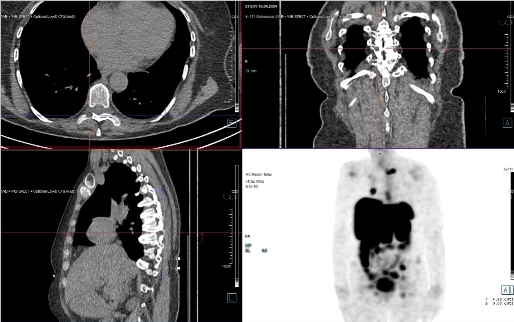

/ Obr. č. 8: Fúze SPECT/CT 24 hod. po aplikaci OctreoScanu. /

/ Obr. č. 9: Fúze SPECT/CT 24 hod. po aplikaci OctreoScanu. /

/ Obr. č. 10: Fúze SPECT/CT 24 hod. po aplikaci OctreoScanu. /

Popis: pozorujeme patologická ložiska zvýšené depozice radiofarmaka-nově nekontrastně ve více LU v levém nadklíčku, v jedné parasternální LU vpravo (úroveň Th6) vel. 10 mm, v LU v dolním mediastinu prekardiálně cca 17 mm, tomograficky zachycena chabě zvýšená akumulace RF v Th páteři v úrovni obratlového těla Th7 a Th8 (v ldCT bez patologického korelátu, nově však v ldCT obraze zjištěna v. s. lýza pravého postranního výběžku obratle Th8), v levém jaterním laloku - S4b, v pravém jaterním laloku - S5 a S6, v LU paraaortálně v úrovni L2/3 15,5 mm - dnes okrsek nápadnější, chabě v levé kosti kyčelní dorsálně při SIS - částečná regrese od min. vyšetření.

Nález svědčí pro přítomnost vícečetných patologických ložisek zvýšené denzity somatostatinových receptorů ve výše uvedených lokalizacích. Ve srovnání s posledním vyšetřením jsou detekována nová ložiska v levém nadklíčku a mediastinu, susp. diskrétní nález i v Th páteři (obratel Th7 a Th8) se zachycenou lýzou postranního výběžku obratle Th8 vpravo v CT obraze, částečná regrese okrsku v levé kosti kyčelní oproti minulému vyšetření.

U nyní 70leté ženy s neuroendokrinním tumorem nejasného primárního zdroje prokazujeme progresi nálezu oproti vyšetření před 22 měsíci.